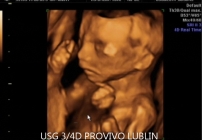

USG 4D Lublin – obraz dziecka w czasie rzeczywistym

USG 4D pokazuje obraz podobny do badania 3D, ale dodatkowo rejestruje go w czasie rzeczywistym. Oznacza to, że rodzice mogą obserwować ruchy dziecka, mimikę twarzy i zachowanie płodu niemal jak podczas podglądu na żywo.

Dla wielu przyszłych rodziców jest to niezwykle ważny i wzruszający moment, ponieważ po raz pierwszy mogą zobaczyć swoje dziecko w ruchu jeszcze przed narodzinami. Aktualna treść strony PROVIVO również podkreśla ten emocjonalny wymiar badania 4D.